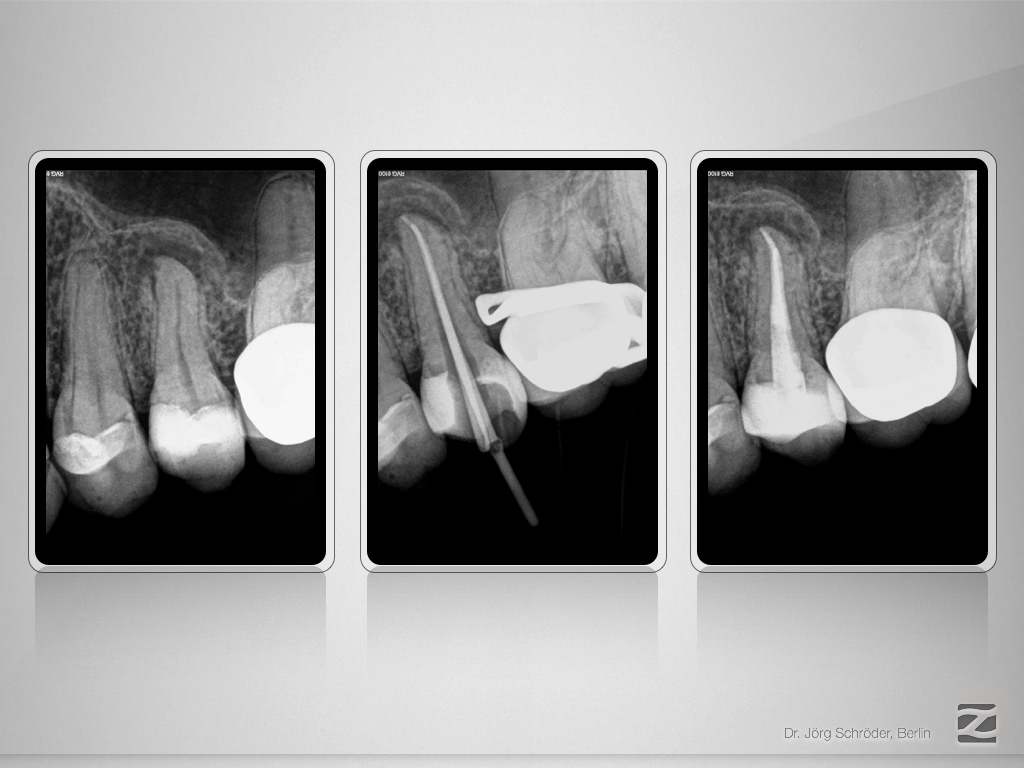

25D.009

Tiefe Gabelung